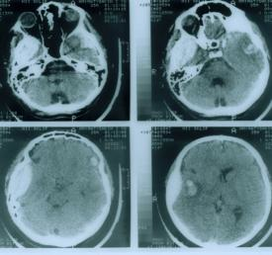

эпидуральные (расположенные над твёрдой мозговой оболочкой, в 20% случаев), субдуральные (между твёрдой мозговой оболочкой и паутинной оболочкой, 70-80%), внутримозговые (в белом веществе мозга и внутрижелудочковые (в полости желудочков мозга) гематомы; затем вдавленные переломы костей свода черепа (особенно проникновение костных отломков на глубину свыше 1 см);

В большинстве случаев отмечается потеря сознания в момент травмы. В последующем сознание может восстанавливаться. Период восстановления сознания называется светлым промежутком. Спустя несколько часов или суток больной вновь может впасть в бессознательное состояние, что, как правило, сопровождается нарастанием неврологических нарушений в виде появления или углубления парезов конечностей, эпилептических припадков, расширения зрачка с одной стороны, урежения пульса (частота менее 60 в минуту) и т.д.

По темпу развития различают острые внутричерепные гематомы, которые проявляются в первые 3 суток с момента травмы, подострые - клинически проявившиеся в первые 2 недели после травмы и хронические, которые диагностируются после 2 недель с момента травмы.